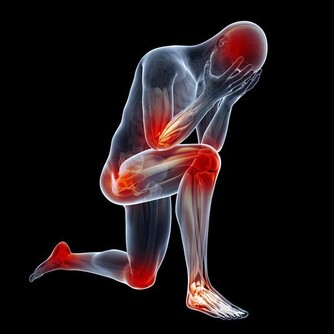

2. 你的腹部疼痛

腹痛是胰腺癌和急性胰腺炎最常見的症狀之一,這是一種致命的炎症。但是具體病症不同,疼痛部位也不同。如果疼痛在“輻射”到背部正中或下部之前,似乎是從腹部中央開始的,並且已經持續數週,這可能是胰腺癌的徵兆。醫生通常會誤將胰腺癌引發的疼痛當作胃酸反流或其他胃腸道疾病,並給你開質子泵抑製劑進行治療。如果你正在服用此類藥物卻不見效,更要引起注意。

另一方面,如果疼痛突然出現,並且集中在腹部中央,這通常與急性胰腺炎有關。無論哪種情況,都先不要驚慌失措。畢竟,許多健康問題,包括嚴重的也不嚴重的,都會導致腹痛。